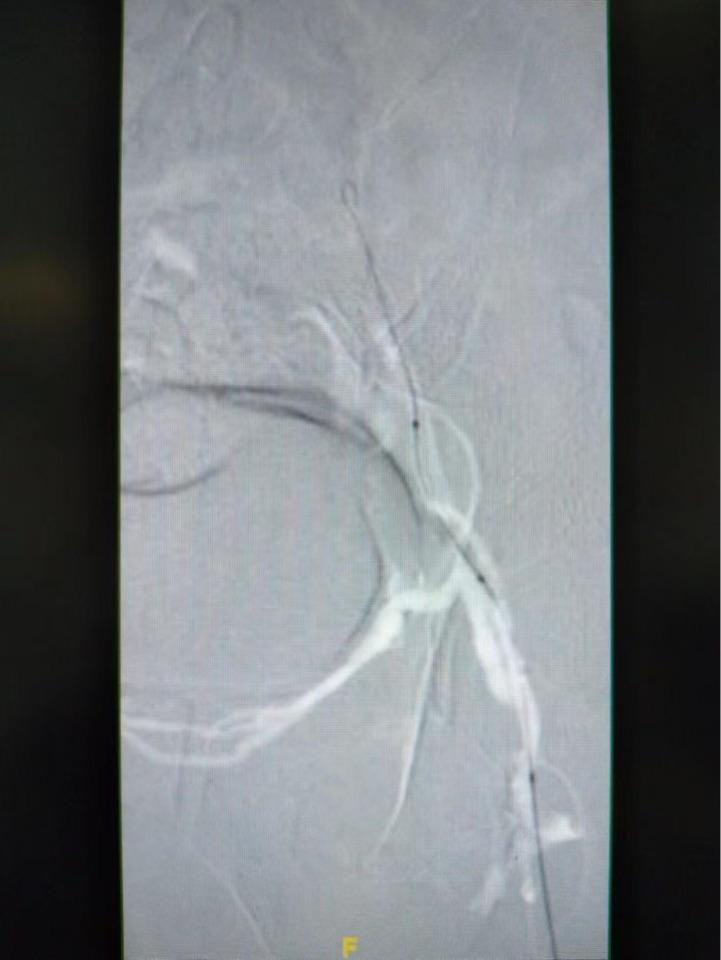

高压球囊扩张,切迹明显